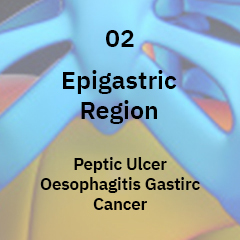

GERD/ Acid reflux is a very common condition affecting people of all age groups. Acid Reflux or GERD is characterized by a burning pain a.k.a heartburn as it is generally called, felt internally around the lower chest area.

Esophageal cancer is a cancer that happens in the esophagus. The esophagus is a long, hollow tube that begins at the throat and ends at the stomach.

When upper digestive tract shows symptoms of upset, pain, or early or prolonged fullness. This is described as “functional” because there is nothing structurally wrong with the upper digestive area, but bothersome symptoms persist.